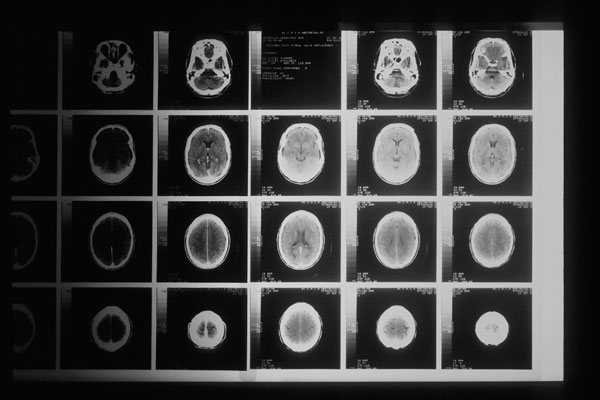

神經(jīng)母細(xì)胞瘤被稱作“兒童腫瘤之王”,是好發(fā)于兒童的一種顱外實(shí)體腫瘤。在中國,兒童神經(jīng)母細(xì)胞瘤發(fā)病率約為1/10萬,每年新發(fā)患兒人數(shù)約為2500例。

神經(jīng)母細(xì)胞瘤的發(fā)病年齡通常在15歲以下,有的患者發(fā)病時(shí)甚至不到2歲,其中超過半數(shù)是高危神經(jīng)母細(xì)胞瘤。